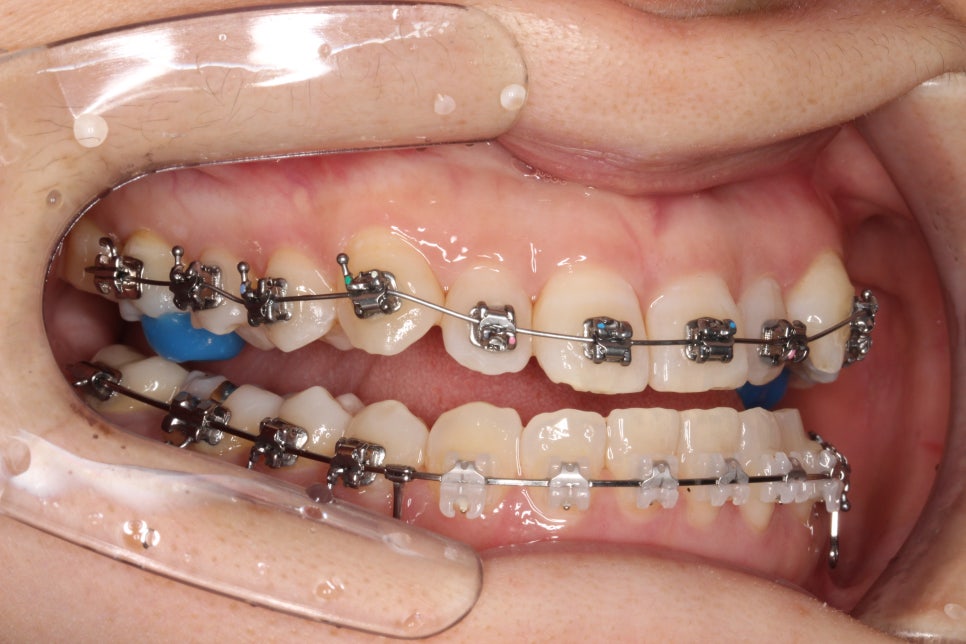

치료를 시작한지 얼마 되지 않았을 때의 모습입니다.

아래쪽은 미니스크류를 식립하여 당기고 있고, 앞니가 넘어올 수 있게 어금니에 #바이트블록 을 올렸습니다.

밥먹을 때 힘드셨을 겁니다 ㅠ

치료기간은 조금 길게 걸렸지만 앞니 관계는 예쁘게 마무리

교합도 잘 마무리 되었고, 현재는 화살표 부분의 임플란트를 완성하기 위해 기다리는 중입니다.